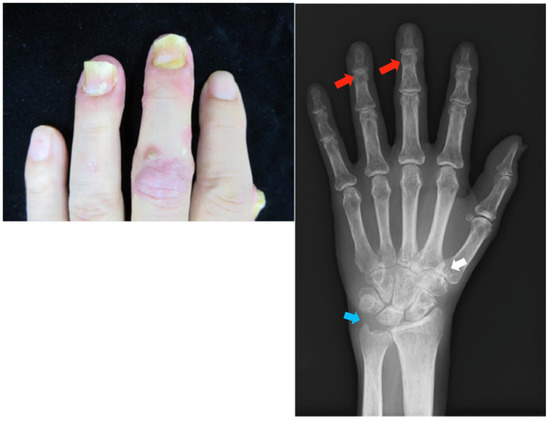

2.3. Case 3

Patient: Woman in her 60s